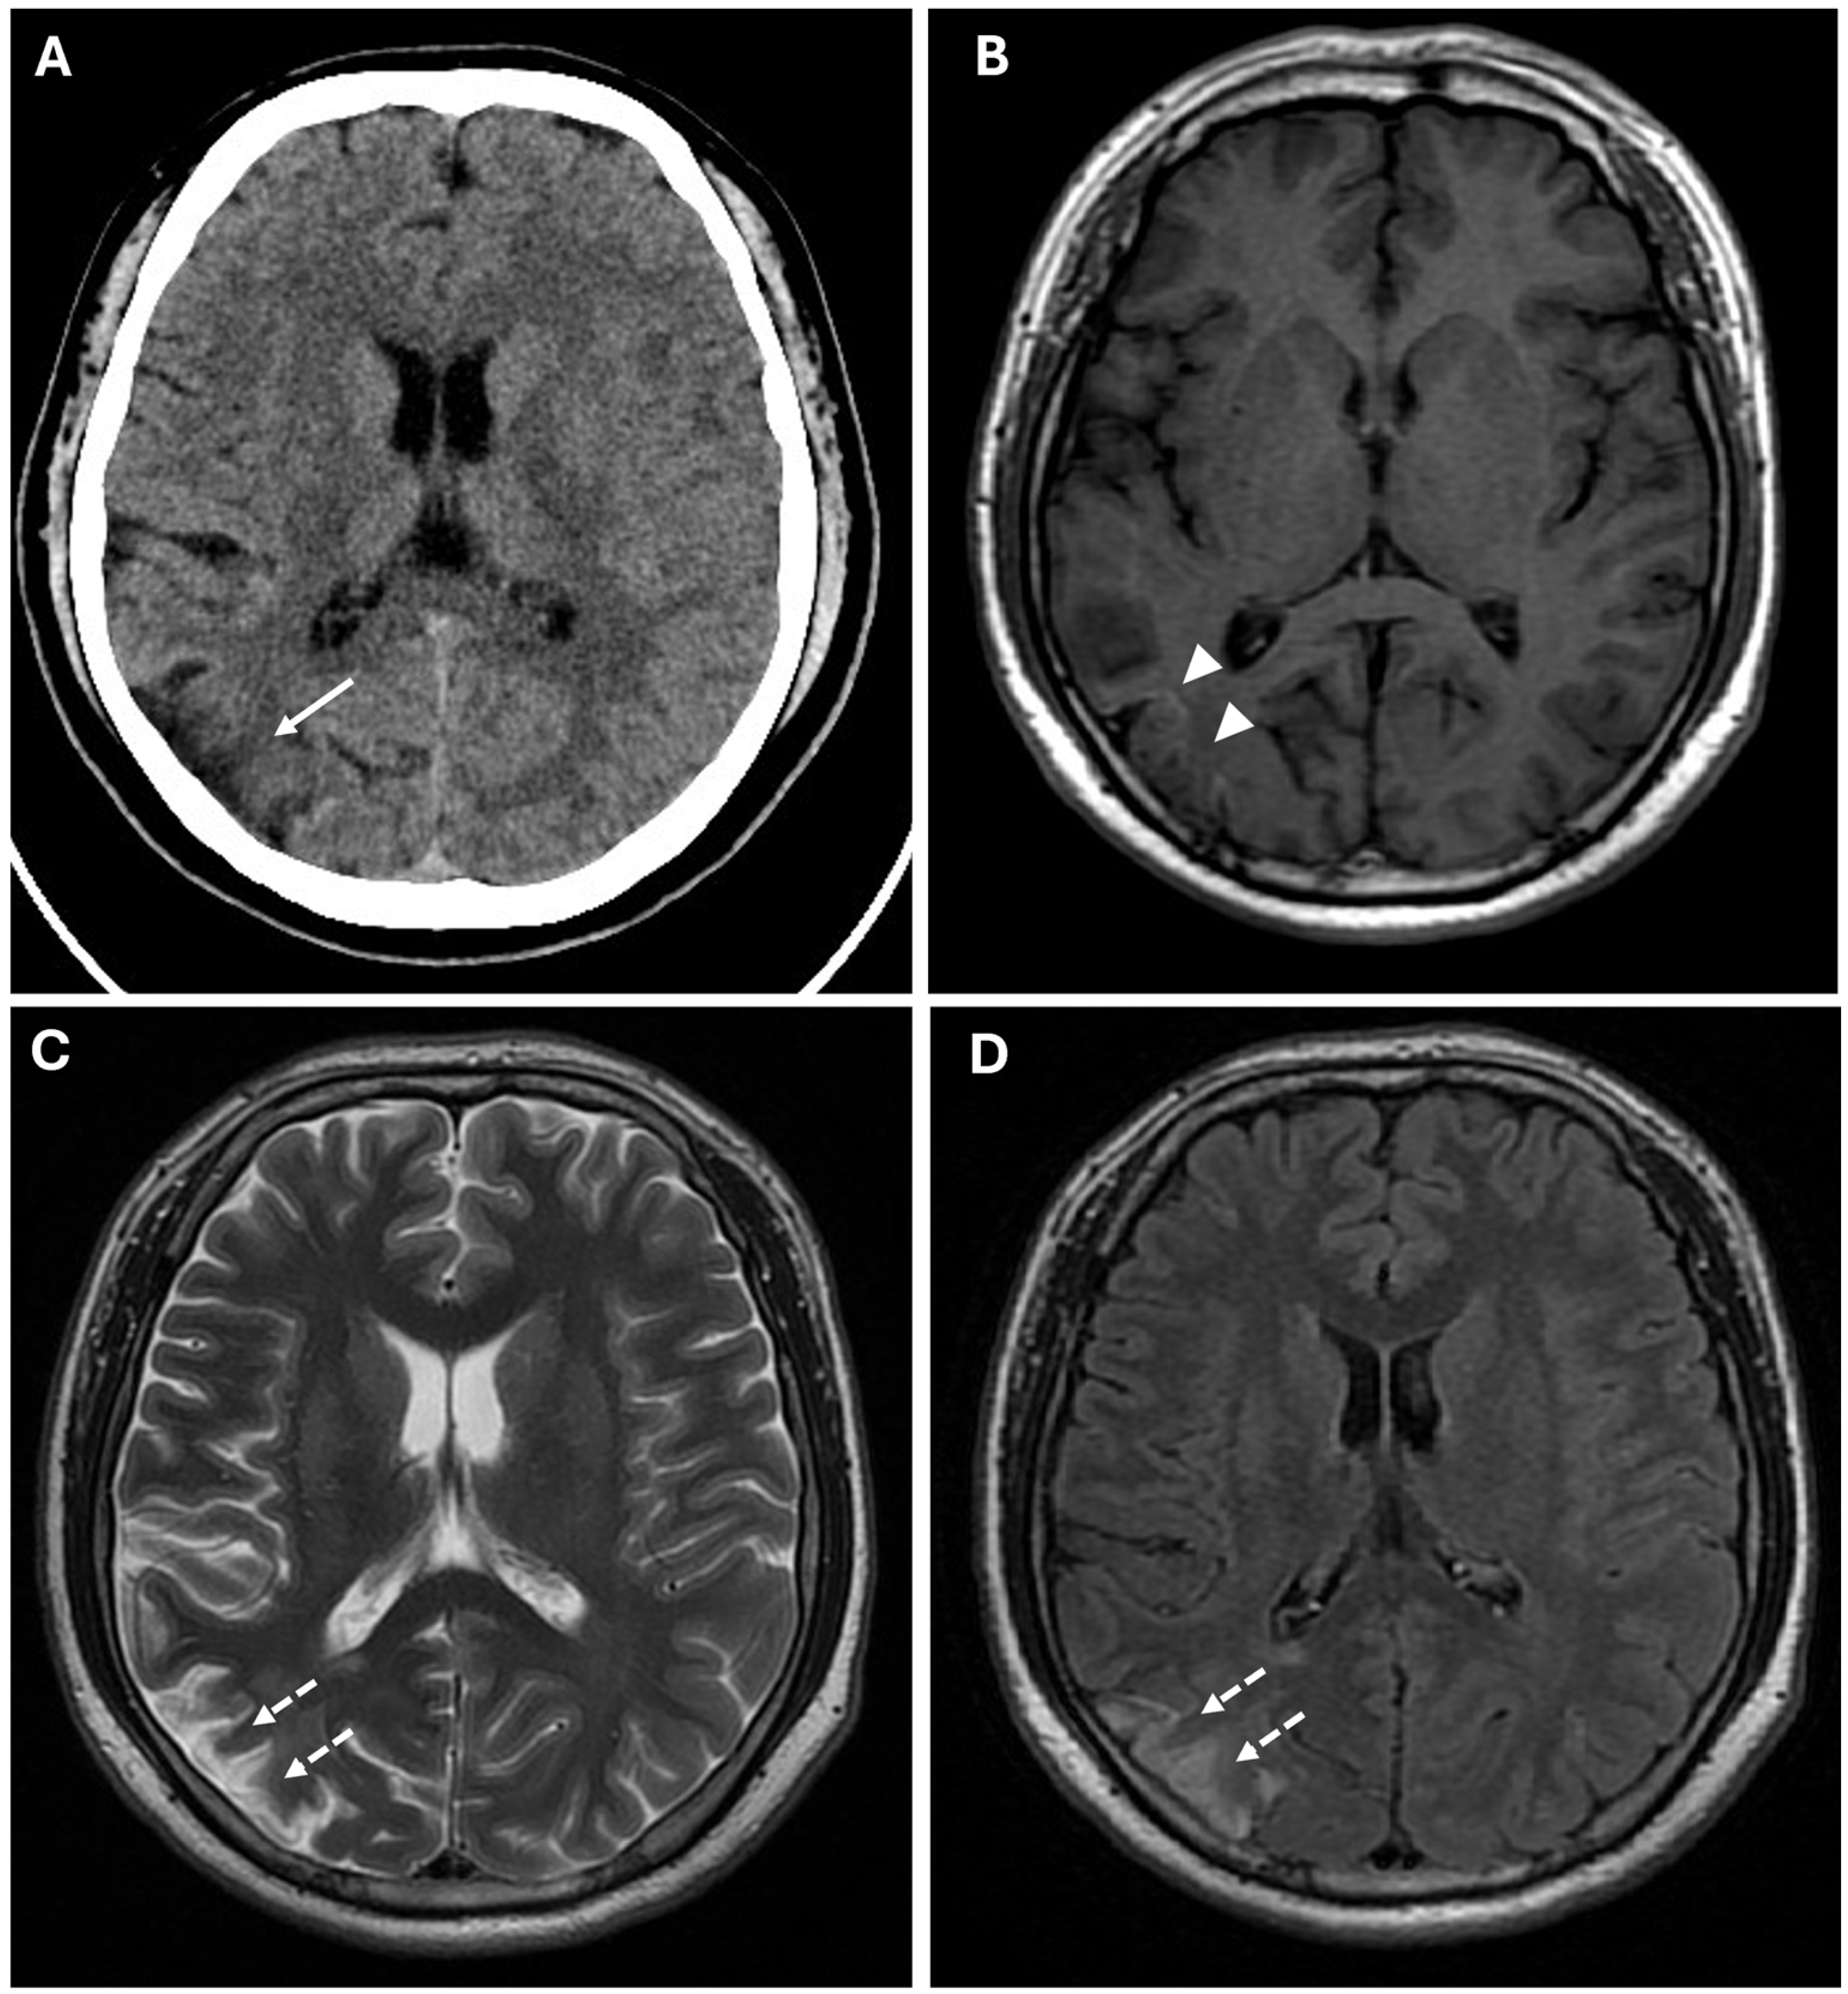

Figure 3. Chronic ischemic lesions. (A) A non-enhanced CT image in axial view shows a hypodensity area in the right frontal and parietal lobes with atrophic brain cortex (white arrow). (B) Axial T1-weighted spin echo sequence shows mild linear hyperintensity in the right parietal lobe, coherent with cortical laminar necrosis (white arrowheads). (C,D) Axial T2-weighted (C) and FLAIR (D) sequences show right parietal and periventricular areas of hyperintensity compatible with subacute-chronic ischemic lesions (white dotted arrows).

Prominent leptomeningeal collaterals with slow flow, resulting in high signal intensity on FLAIR sequences, were detected in the subarachnoid spaces of the left hemisphere (“ivy sign”) (Figure 4).

Figure 4. The Ivy sign in the left-brain hemisphere. (A) Axial 2D FLAIR sequence shows linear hyperintensity along the cortical sulci of the left hemisphere (white arrowheads); note a subacute ischemic lesion in the right parietal lobe (white arrow). (B) CTA Maximal Intensity Projection (MIP) shows prominent leptomeningeal collaterals in the left hemisphere, with abnormal enhancement of blood vessels, “ivy-like” (white arrowheads); the absence of opacification of distal branches of the right MCA (white arrow) was consistent with recent ischemic stroke in the right parietal lobe vascular territory.